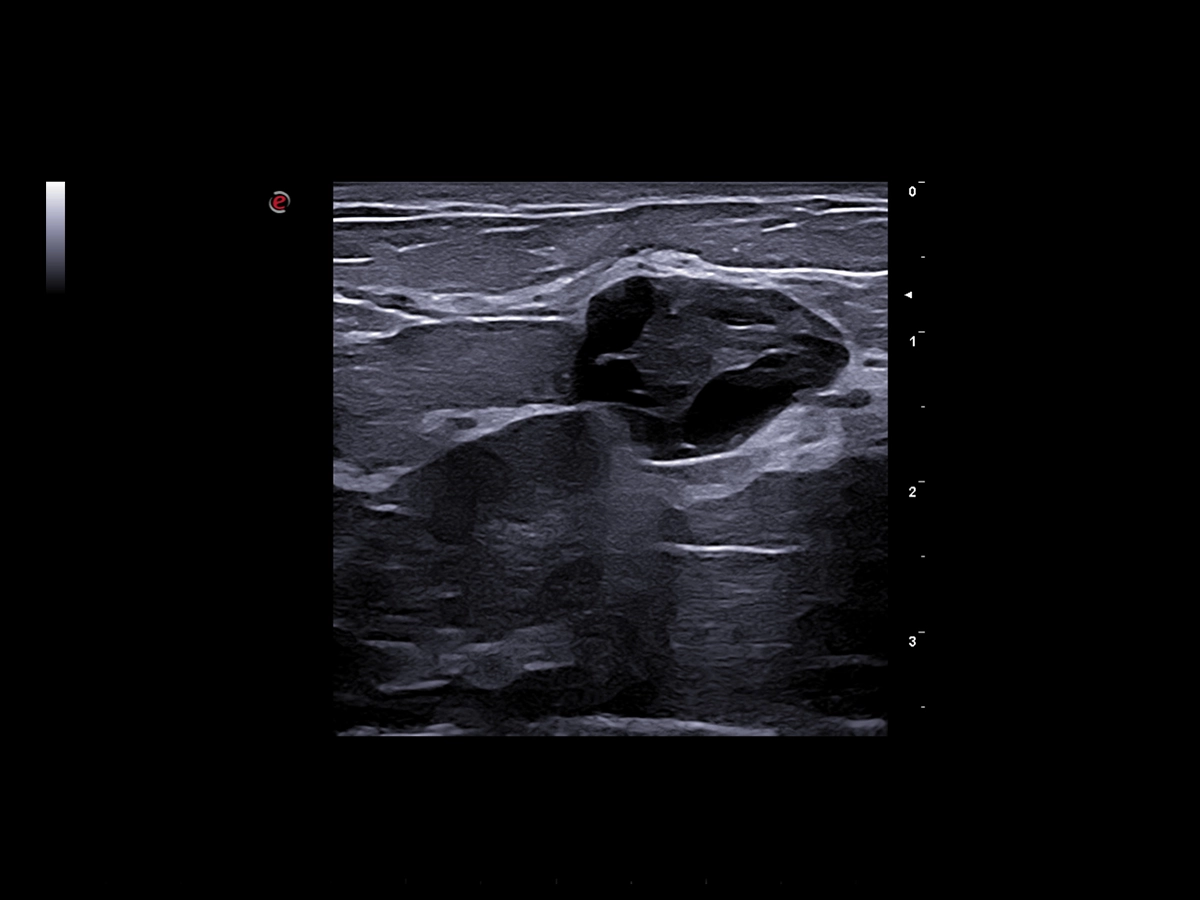

Breast clinical image